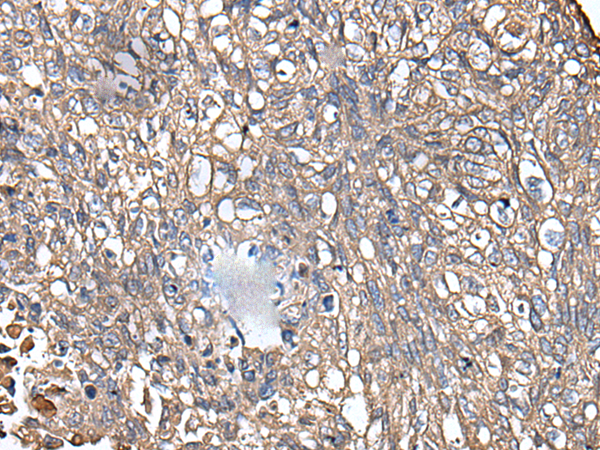

IHC positive control: |

Human prostate cancer and human lung cancer |